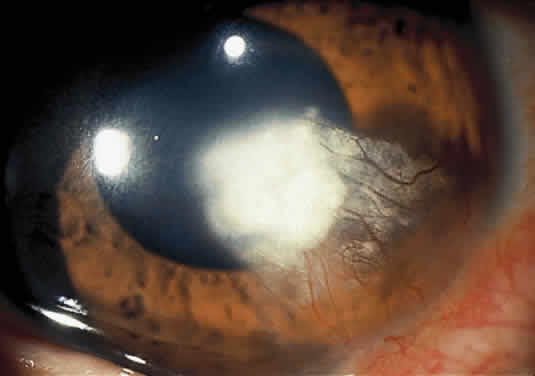

Nonsystemic Familial Type. Lattice corneal dystrophy (Biber-Haab-Dimmer) is usually considered to be a localized amyloidosis of the cornea and could be classified as a special type of primary localized autosomal dominant amyloidosis (see corneal dystrophies section) (Fig. 6).78 Rarely, a form of primary familial amyloidosis of the cornea may occur. The lesions appear as centrally located, raised, gelatinous masses with a mulberry-like surface (Fig. 7).79

CONJUNCTIVA. Clinically detectable conjunctival involvement is not a feature of systemic amyloidosis. However, nonfamilial amyloidosis confined to the conjunctiva has been reported as an example of primary amyloidosis. Conjunctival amyloidosis is often asymptomatic and may be present for years before the patient seeks medical attention. Typically, there is a discrete, nonulcerative, yellow, waxy, firm, nontender subconjunctival swelling (Fig. 8). This may be located in the palpebral fornix or bulbar conjunctiva, including the limbal area. The conjunctival area is usually smooth but may be friable and may show recurrent bleeding. However, antecedent local diseases have been incriminated in this amyloid deposition.77